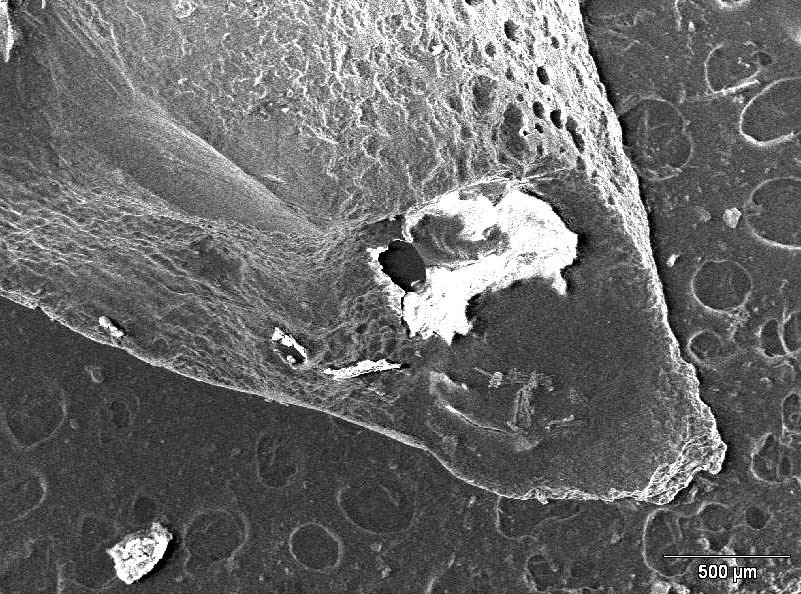

Resorption following infection may affect both the coronal and apical fragments. Additionally, involved root surfaces include the outer surfaces and it is not uncommon to for internal resorption to occur. Scanning electron microscopy (SEM) is an important technological aid for the analysis of the surface of the roots that are removed during endodontic surgery. Scanning electron microscopy enables the analysis of root morphology and the description of anatomy after resorption. The images presented in this review were captured with a SEM Hitachi Model S2460N (Hitachi, Tokyo, Japan) microscope with an acceleration voltage of 20 kV beam, and current of approx. 70 µA. The images present the SEM analysis of the surfaces of the fractured apical portion of #21 and the excised apical portion of #11. Interestingly, the area of the fracture of the apical fragment shows a geometric organization with vertical faults. As demonstrated earlier, fracture resistance is influenced by several factors, such as density, the diameter and the degree of obliteration depending on the patient’s age, presence of dentinal tubules and dentin microcomposition, which displays lower fracture resistance in deeper layers.28, 29

Figure 5 and Figure 6 show the root apexes of 2 excised fragments. On the root surface of tooth #21 (without root fracture), clear external resorption areas are visible even at lower magnification (×40); the same areas of resorption are less visible on the surface of tooth #11 at a higher magnification (×110). This indicates that the degree of external resorption was higher for #21 than #11.

The areas of resorption of tooth #11, that presented with the fracture of the third apical portion of the root, are more limited and shallower than those observed on the root surface of tooth #21, which has been completely avulsed, where the resorption was more aggressive and the lesions appeared to be diffuse, destroying the root surface (Figure 7, Figure 8).

Figure 9 and Figure 10 show the surface of the 2 removed apical fragments of tooth #21 and #11, respectively. Interestingly, the surface of the fracture that is visible on the apical root fragment removed during the apicoectomy of #11 is characterised by the presence of regular steps, reflecting a repetitive pattern.